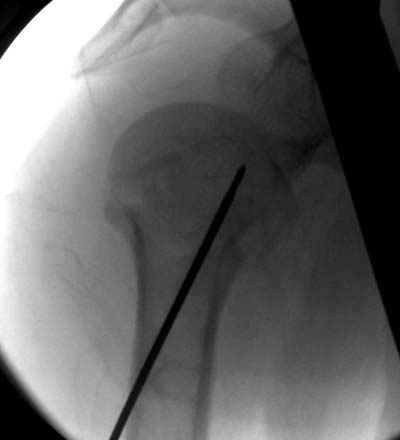

Пока я пользуюсь методикой принятой у нас (методика Сиэтла), также перкутанный спицевой метод, только сцицы 2.8 мм с резбой на конце.

Здесь случай перелома-вывиха плеча, больному 56 лет, после "дважды" закрытой неудачной репозиции, опять же ургентно взяли в операционную, после полного общего обезболивания попытались сделать репозицию, и фиксацию провели спицами.

Больной находился в повязке, примерно напоминяющей косыночную, рекомендованы движения в локтевом суставе и маятниковые движения в плече, спицы удалены в три недели (были случаи миграции)

Больной амбулаторный, предупрежден на случай осложнения АВН головки.